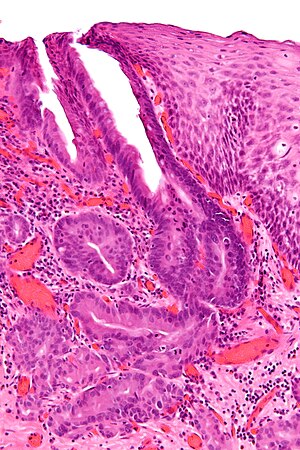

Esophageal adenocarcinoma. H&E stain. | |

| LM | "invading" cell clusters or glands (gland cribriforming (more than rare) or desmoplasia or submucosa invasion); nuclear atypia of malignancy (variation of size, shape, staining), +/-mitoses |

Microscopic

Features:

- Adenocarcinoma:

- "Invading" cell clusters or glands.

- Cribriforming (more than rare) or desmoplasia or "deep" invasion (into submucosa).

- Nuclear atypia of malignancy:

- Size variation.

- Shape variation.

- Staining variation.

- +/-Mitoses (common).